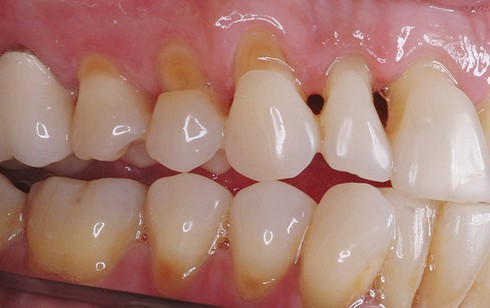

Răng bị bào mòn. (Ảnh minh họa) |

Theo TS-BS Phạm Thị Thu Hằng (Khoa Răng - Bệnh viện Trung ương Quân đội 108), mòn-tiêu cổ răng là hiện tượng mất tổ chức cứng của răng ở vị trí gần đường nối men ngà. Biểu hiện dễ nhận biết là cổ răng bị khuyết, lõm sâu có hình chữ V (còn gọi là lõm hình chêm), hay gặp nhất ở mặt ngoài cổ răng hàm nhỏ ở hàm trên, ngoài ra còn thấy ở răng cửa và răng hàm lớn.